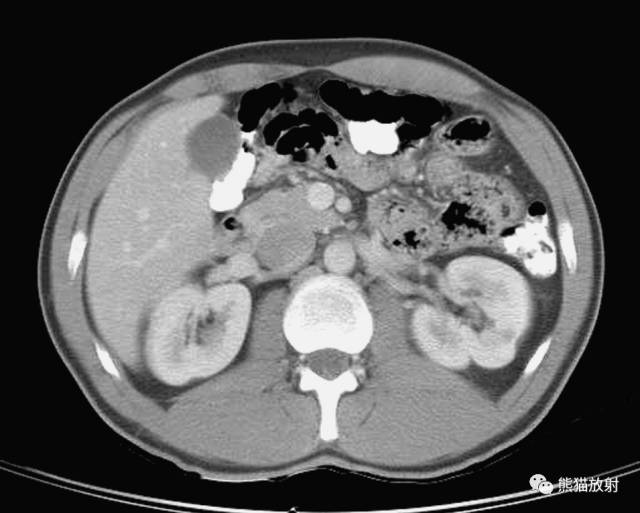

第十层

1、肝脏;2、右肾静脉;3、结肠右曲;4、回肠;5、下腔静脉;6、横结肠;7、十二指肠;8、右侧睾丸动脉;9、肠系膜上动脉及静脉;10、空/回肠动/静脉;11、左侧睾丸动脉;12、左肾静脉;13、空肠;14、腹横肌;15、内斜肌;16、降结肠;17、外斜肌;18、右肾;19、肾窦(脂肪组织);20、腰方肌;21、腰大肌;22、右侧腰静脉;23、膈肌;24、椎管;25、棘肌;26、腰椎;27、腹主动脉;28、最长肌;29、肾盂;30、髂肋肌;31、背阔肌;32、肝肾隐窝;33、网膜囊;34、肋间淋巴结;35、横结肠系膜;36、腰淋巴结;37、肠系膜;38、肾门;39、左侧肠系膜结肠沟;40、肾筋膜;41、左侧结肠旁沟。